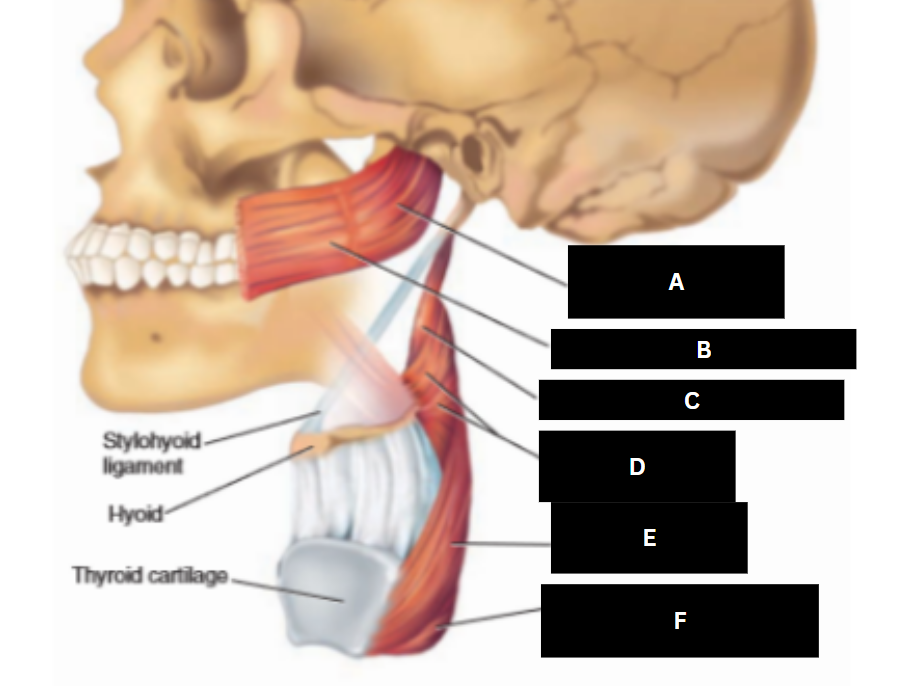

Stylopharyngeus

A

Styloglossus

B

Stylohyoid

C

Cricopharyngeus

D

Superior pharyngeal constrictor

E

Middle pharyngeal constrictor

F

Pharyngeal raphe

G

Inferior pharyngeal constrictor

H